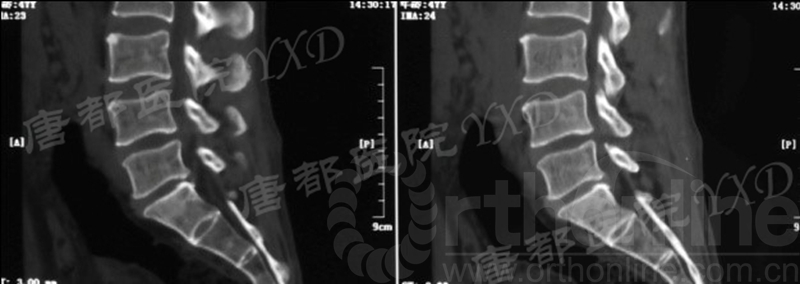

影像学检查:

诊断:腰椎椎间融合术后融合器后移

手术方案:显微镜辅助MI-TLIF腰椎翻修术

术中视频:http://api.orthonline.com.cn/attach/Case3.mp4(术中发现因前次手术全椎板及关节突切除,TLIF的第一步,即关节突关节的定位落脚点难以找到。显微镜下通过Kambin三角解剖位置,进行从外至内的解剖,寻找cage尾端;此外,因大量瘢痕渗血,难以进行充分止血;但在显微镜的照明和放大视野下,操作均可在不伤及神经的前提下进行。由于终板骨质吸收,椎间隙塌陷,导致术野内可同时看到出行根和走行根。而在显微镜下,能够通过调整景深和视线角度,精准充分处理椎间隙骨性终板。无手术并发症)